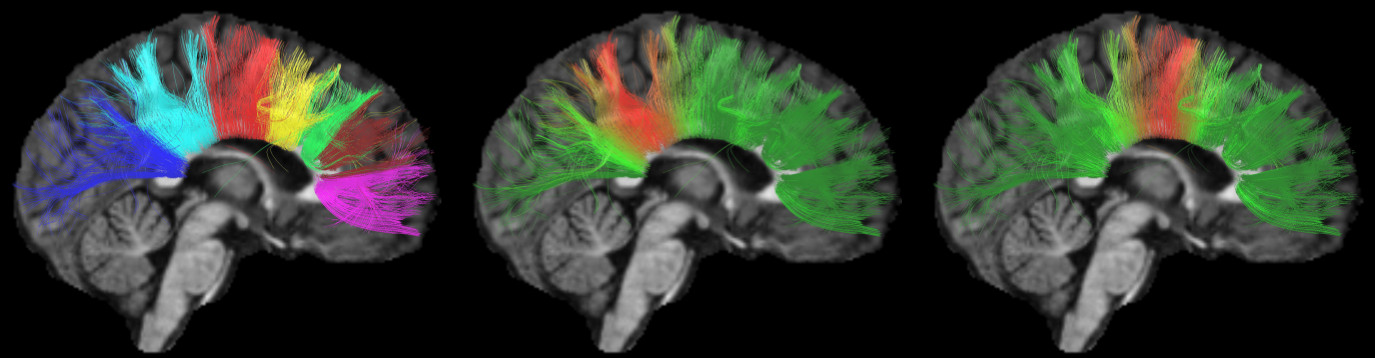

Refer to caption

Figure 4: Membership level of streamlines to two different bundles (left and center), and importance of each streamline in defining the prototype of a bundle (right). Blue means a null membership/importance, while non-zero values are represented by a color ranging from green (lowest value) to red (highest value).

To illustrate the soft clustering of KSC, Fig. 4 (left) and (center) show the membership level of streamlines to two different bundles. Streamline colors in each figure correspond to the values of a row in 𝐖𝐖\mathbf{W} normalized so that the minimum is 0 (blue) and the maximum is 111 (red). We observe streamlines having a membership to both bundles (e.g., orange-colored streamlines in the left image), reflecting the uncertainty of this part of the clustering. In Fig. 4 (right), we show the importance of each streamline in defining the prototype of a bundle, using the normalized value of a column in 𝐀𝐀\mathbf{A} as colors. It can be seen that only a few streamlines are used to define this bundle, confirming the sparsity of 𝐀𝐀\mathbf{A}.